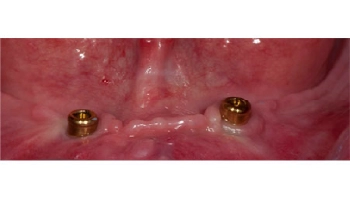

Implant retained lower denture

Before and after photos of an implant retained lower denture. Comparison of lower denture before and after implant retention.

4 Implant Retained Maxillary Denture

Before image of a maxillary denture, showing missing teeth. After image of a maxillary denture supported by four implants. Before and after images of a maxillary denture with implants.